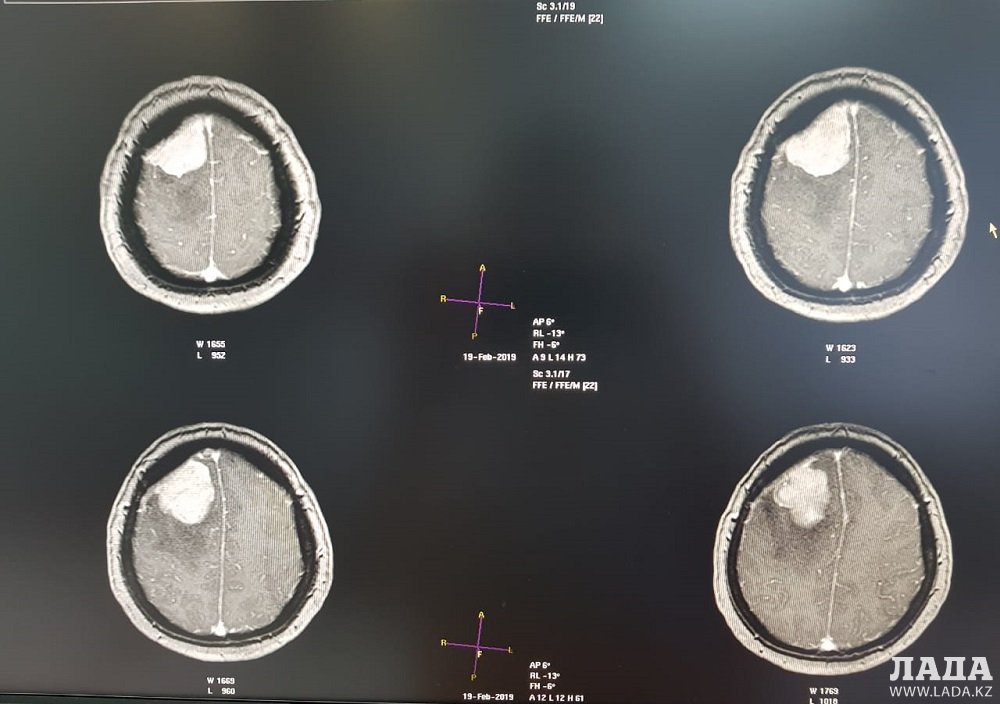

Опухоль мозга диаметром семь сантиметров удалили пенсионерке врачи Мангистау

Дополнительное обследование в аппарате компьютерной томографии (КТ) и магнитно-резонансной томографии (МРТ) показали у пенсионерки наличие отека правого полушария головного мозга.

- Врачи 28 февраля провели операцию по удалению опухоли в правой лобно-теменной области путем костно-пластической трепанации черепа пациентки. Операция прошла успешно, без осложнений, опухоль удалена полностью, - отметили в пресс-службе управления здравоохранения.